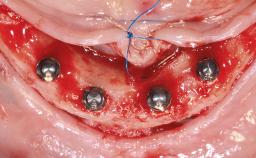

Conventional Loading of Four Implants in the Edentulous Maxilla and Restoration with a Bar-Supported Overdenture

A 64-year-old male patient was referred to the University Medical Center Groningen, The Netherlands, for dental implant treatment. The patient had been edentulous in both the maxilla and mandible for 25 years. During these 25 years, three conventional dentures had been fabricated, the most recent one being 2 years old. The patient complained of inadequate retention and stability of his maxillary and mandibular dentures. The esthetic aspect was of medium importance to the patient. His medical history was unremarkable.